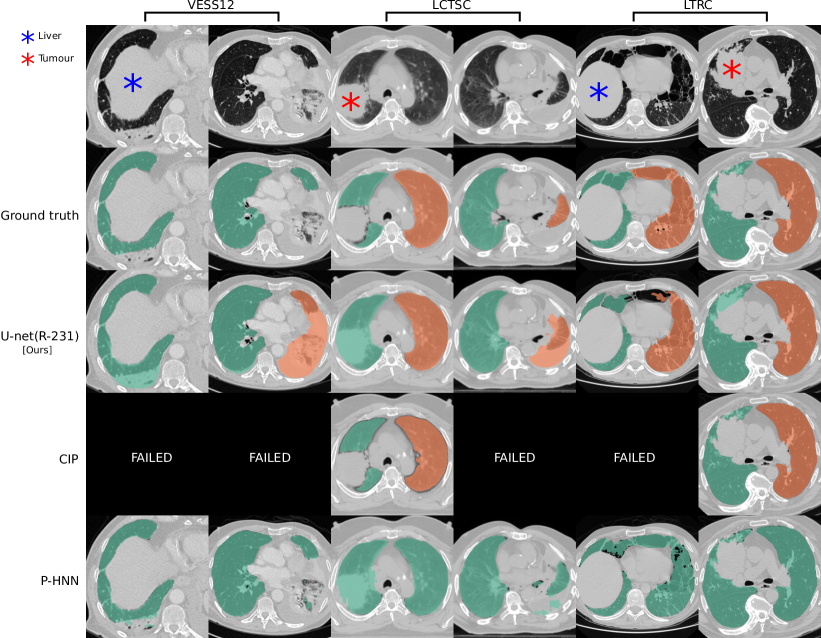

Models trained on routine data achieve improved evaluation scores compared to models trained on publicly available study data. U-net, ResU-net, and Deeplab v3+ models, when trained on routine data (R-36), yielded the best evaluation scores on the merged test dataset (All, n = 62). The U-net yields mean DSC, HD95, and MSD scores of 0.96 0.08, 9.19 18.15, 1.43 2.26 when trained on R-36 [U-net(R-36)] and 0.92 0.14, 13.04 19.04, 2.05 3.08 when trained on VISC-36 (R-36 versus VISC-36, p = 0.001, 0.046, 0.007) or 0.94 0.13, 11.09 22.9, 2.24 5.99 when trained on LTRC-36 (R-36 versus LTRC-36, p = 0.024, 0.174, 0.112). This advantage of routine data for training is also reflected in results using other combinations of model architecture and training data. Table III lists the evaluation results in detail. We determined that the influence of model architecture is marginal compared to the influence of training data. Specifically, the mean DSC does not vary for more than 0.02 when the same combination of training and test set was used for different architectures (Table III). Compared to readily available trained P-HNN model, the U-net trained on the R-231 routine dataset [U-net(R-231)] yielded mean DSC, HD95, and MSD scores of 0.98 0.03, 3.14 7.4, 0.62 0.93 versus 0.94 0.12, 16.8 36.57, 2.59 5.96 (p = 0.024, 0.004, 0.011) merged test dataset (All, n = 62). For comparison with the CIP-algorithm, only volumes for which the algorithm did not fail were considered. On the merged dataset (All, N=62) the algorithms yielded mean DSC, HD95, and MSD scores of 0.98 0.01 ,1.44 1.09 ,0.35 0.19 for the U-net(R213) compared to 0.96 0.05, 4.65 6.45, 0.91 1.09 for CIP (p = 0.001, 0.001, 0.001). Detailed results are given in Table IV. Fig. 2 shows qualitative results for cases from the routine test sets and Fig. 3 shows cases for which the masks generated by the U-net(R-231) model yielded low DSCs when compared to the ground truth. We created segmentations for the 55 cases of the LOLA11 challenge with the U-net(R-231) model. The unaltered masks yielded a mean overlap score of 0.968 and with dense areas removed 0.977. Table V and Fig. 4 show results for tumour overlap on the 318 volumes of the Lung1 dataset. U-net(R-231) covered more tumour volume mean/median compared to P-HNN (60%/69% versus 50%/44%, p 0.001) and CIP (34%/13%). Qualitative results for tumour cases for U-net(R-231) and P-HNN are show in Figs. 5b, c. We found that 23 cases of the Lung1 dataset had corrupted ground-truth annotation of the tumours (Fig. 5d). Fig. 5e shows cases with little or no tumour overlap achieved by U-net(R-231).

We showed that training data, sampled from the clinical routine, improves generalizability to a wide spectrum of pathologies compared to public datasets. We assume this lies in the fact that many publicly available datasets do not include dense pathologies such as severe fibrosis, tumour, or effusions as part of the lung segmentation. Further, they are often provided without guarantees about segmentation quality and consistency. While the Anatomy3 dataset underwent a thorough quality assessment, the organisers of the VESSEL12 dataset merely provided lung segmentations as a courtesy supplement for the task of vessel segmentation, and within the LCTSC dataset, “tumour is excluded in most data” and “collapsed lung may be excluded in some scans” [5]. Results indicate that that both, size and diversity of the training data, are relevant. State-of-the-art results can be achieved with images from only 36 patients which is in line with previous works [41] achieving a mean DSC of 0.99 on LTRC test data using the U-net(R-36) model. A large number of segmentation methods are proposed every year, often based on architectural modifications [31] of established models. Isensee et al. [31] showed that such modified design concepts do not improve, and occasionally even worsen, the performance of a well-designed baseline. They achieved state-of-the-art performance on multiple, publicly available segmentation challenges relying only on U-nets. This corresponds to our finding that architectural choice had a subordinate effect on performance. At the time of submission, the U-net(R-231) achieved the second highest score among all competitors in the LOLA11 challenge. In comparison, the first ranked method [22] achieved a score of 0.980 and a human reference segmentation achieved 0.984 [41]. Correspondingly, the U-net(R-231) model achieved improved evaluation measures (DSC, HD95, MSD and tumour overlap) compared to two public algorithms. There are limitations of our study that should be taken into account. Routine clinical data vary between sites. Thus, extraction of a diverse training dataset from clinical routine may only be an option for centres that are exposed to a wide range of patient variety. Evaluation results based on public datasets are not fully comparable. For example, the models trained on routine data compared to other datasets yielded lower performance in terms of DSC on the LCTSC test data. However, the lower scores for models trained on routine data in LCTSC can be attributed to the lack of very-dense pathologies in the ground truth masks. Fig. 3 illustrates cases for which the R-231 model yielded low DSC. The inclusion or exclusion of pathologies such as effusions into lung segmentations is a matter of definition and application. While pleural effusions (and pneumothorax) are technically outside the lung, they are assessed as part of lung assessment, and have a substantial impact on lung parenchyma appearance through compression artefacts. Neglecting such abnormalities would hamper automated lung assessment, as they are closely linked to lung function. In addition, lung masks that include pleural effusions greatly alleviate the task of effusion detection and quantification, thus making it possible to remove effusions from the lung segmentation as a post-processing step. We proposed a general lung segmentation algorithm relevant for automated tasks in which the diagnosis is not known beforehand. However, specialized algorithms for specific diseases could be beneficial in scenarios of analyzing cohorts, for which the disease is already known. In conclusion, we showed that accurate lung segmentation does not require complex methodology and that a proven deep-learning-based segmentation architecture yields state-of-the-art results once diverse (but not necessarily larger) training data are available. By comparing various datasets for training of the models, we illustrated the importance of training data diversity and showed that data from clinical routine can generalize well to unseen cohorts, highlighting the need for public datasets specifically curated for the task of lung segmentation. We draw the following conclusions: (1) translating ML approaches from bench to bedside can require the collection of diverse training data rather than methodological modifications; (2) current, publicly available study datasets do not meet these diversity requirements; and (3) generic, semantic, segmentation algorithms are adequate for the task of lung segmentation. A reliable, universal tool for lung segmentation is fundamentally important to foster research on severe lung diseases and to study routine clinical datasets. Thus, the trained model and inference code are made publicly available under the GPL-3.0 license to serve as an open science tool for research and development and as a publicly available baseline for lung segmentation under https://github.com/JoHof/lungmask.